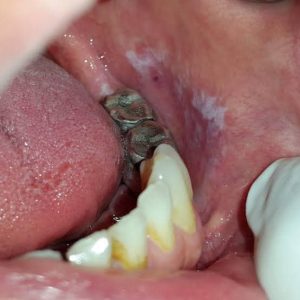

Amalgam Ve Kandidiyazis Candida

Fotoğrafların ortak yönü : amalgam-kandidiyazis

Cıva, Th1 ve Th2 sitokinleri üzerindeki etkisiyle Candida’ya karşı makrofaj ve nötrofil savunmasını inhibe eder.

Candida ayrıca inorganik cıvayı, cıva buharı gibi kan-beyin bariyerini kolayca geçen, nörolojik hasara neden olan ve bağışıklık sistemini zayıflatan yüksek derecede toksik metil cıva formuna metilleştirir.